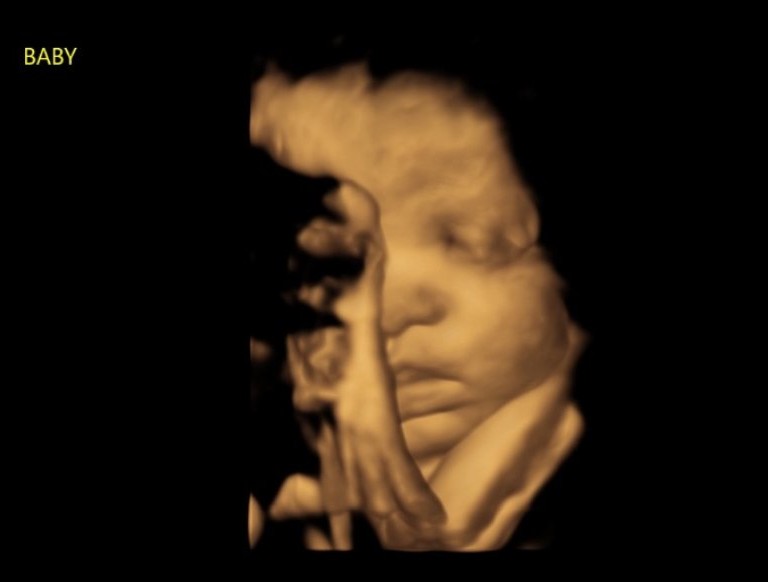

Pregnancy help medical clinics continue to express gratitude and appreciation for the LAUC events as medical teams in attendance return to their clinics ready to be used by the Lord to save lives today through imaging the growing child in the womb, while also planting seeds to save lives for eternity.

Within the pregnancy help medical clinic, generations are saved. One ultrasound at a time.